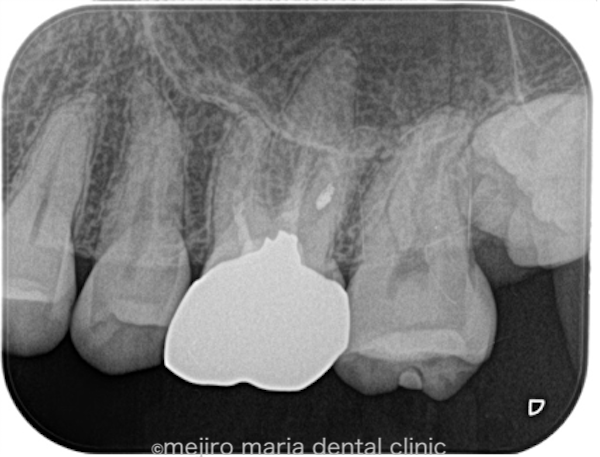

治療後の様子

今後は通常と同じように2年間の経過観察を行い、治療の経過を確認していく予定です。